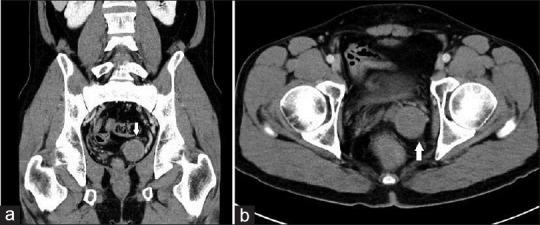

Schwannomas, namely neurilemmomas, are benign nerve sheath tumors and comprise the myelin sheaths around the peripheral nerves. Schwannomas commonly occur in the head and neck, or extremities, less found in the mediastinum and retroperitoneum, and rarely in the pelvis. We report a 40-year-old male presenting with an 18-month history of nocturia and urinary frequency. Transrectal ultrasound revealed a well-defined, 2.81 cm × 3.77 cm in size, homogeneous, hypoechoic mass in the tail of the left seminal vesicle, compatible with the finding of a well-demarcated mass at the left seminal vesicle with homogeneous contrast enhancement on computed tomography. He underwent laparoscopic excision of the mass via da Vinci robotic surgical system. Intraoperative sonography showed that the mass exhibited the majority of hypoechoic density with some hyperechoic spots inside. Pathology reveals schwannoma. Both of erectile and ejaculatory functions were claimed postoperatively. Our case report highlights the potential of either intraoperative or preoperative sonography in the assessment of the seminal vesicle schwannoma.

摘要